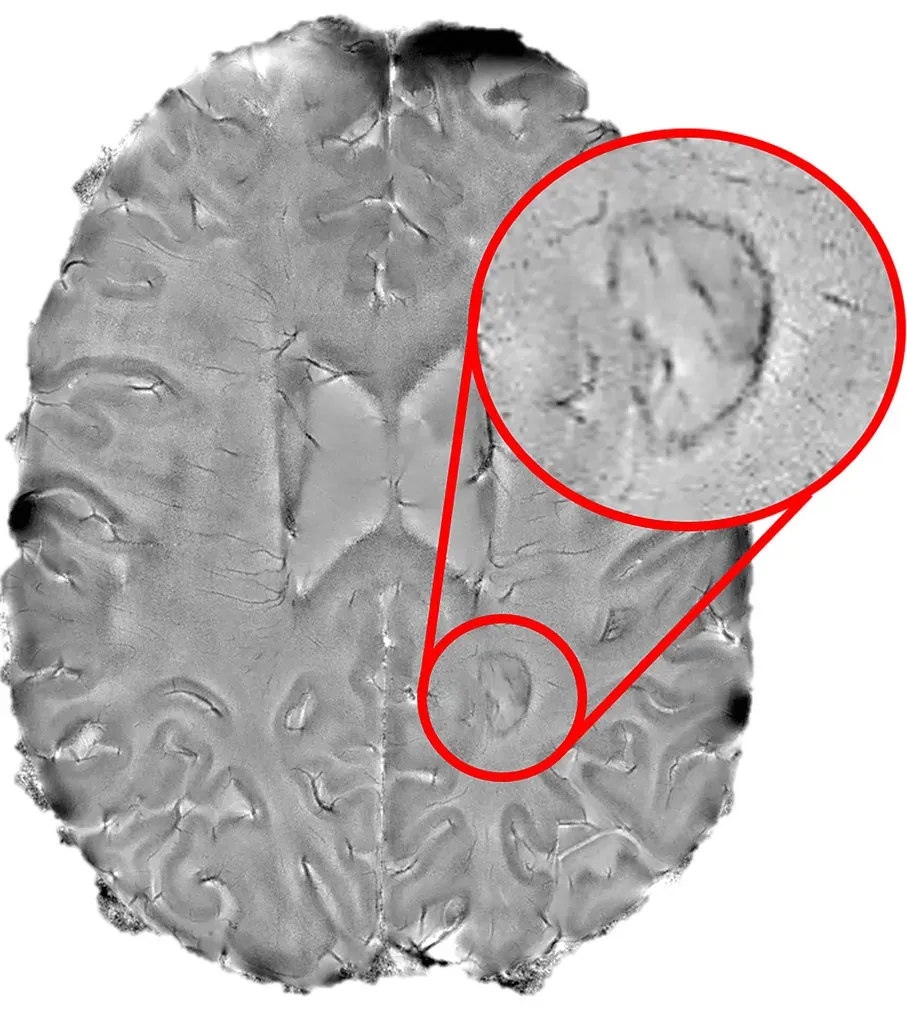

Image Credits: Wikimedia; licensed under CC BY-SA 3.0.

Artificial sweeteners like aspartame, sucralose, and saccharin are linked to oxidative stress and neuroinflammation, disruptions to the blood-brain barrier, and changes in cerebral blood flow, which could accelerate cognitive decline. These aren’t just technical terms from a lab report. They represent real changes happening inside your brain when you consume these substances regularly.

A groundbreaking study found that people who consumed the most low- or no-calorie sweeteners showed a 62% faster global cognitive decline than those who consumed the lowest amount, equivalent to 1.6 years of brain aging. That’s not a small difference. Imagine aging your brain by nearly two years just from your coffee creamer choices.

The study included over 12,000 adults from across Brazil with an average age of 52, and participants were followed for an average of eight years. This wasn’t some rushed, small-scale experiment. People in the highest consumption tier consumed an average of 191 milligrams of artificial sweeteners each day, roughly equivalent to one can of diet soda sweetened with aspartame, which contains around 200 to 300 milligrams.

When researchers analyzed the results by age, they found people under the age of 60 who consumed the highest amounts of sweeteners showed faster declines in verbal fluency and overall cognition. The younger crowd, the ones who think they’re being health-conscious by choosing sugar-free options, might actually be putting their brains at greater risk.

Aspartame is broken down in the gastrointestinal tract into phenylalanine, aspartic acid, and methanol; phenylalanine crosses the blood brain barrier, and it is a precursor of monoamine neurotransmitters dopamine, epinephrine, and serotonin, which regulate memory, mood, motivation, and motor function. Your brain chemistry is being altered every time you consume it.

Aspartame, a widely used artificial sweetener, remains controversial due to neurotoxic risks from its metabolites, and while epidemiological studies link artificial sweeteners to cerebrovascular disease, the molecular mechanisms connecting aspartame to ischemic stroke are unclear. Scientists are still working to understand all the pathways of harm, which means we don’t yet know the full extent of the damage.

A 2025 study suggests that aspartame may interact with several proteins and receptors in the brain, causing multiple interferences that promote hypertension and stroke risk, with researchers suggesting potential incompatibilities between daily aspartame consumption and certain medications meant to lower blood pressure. It’s not just about your coffee anymore. It could interact with medications you’re already taking.

Think about the blood-brain barrier as your brain’s security system. Artificial sweeteners are linked to disruptions to the blood-brain barrier. When that protective wall is compromised, harmful substances that should never reach your brain suddenly have access.